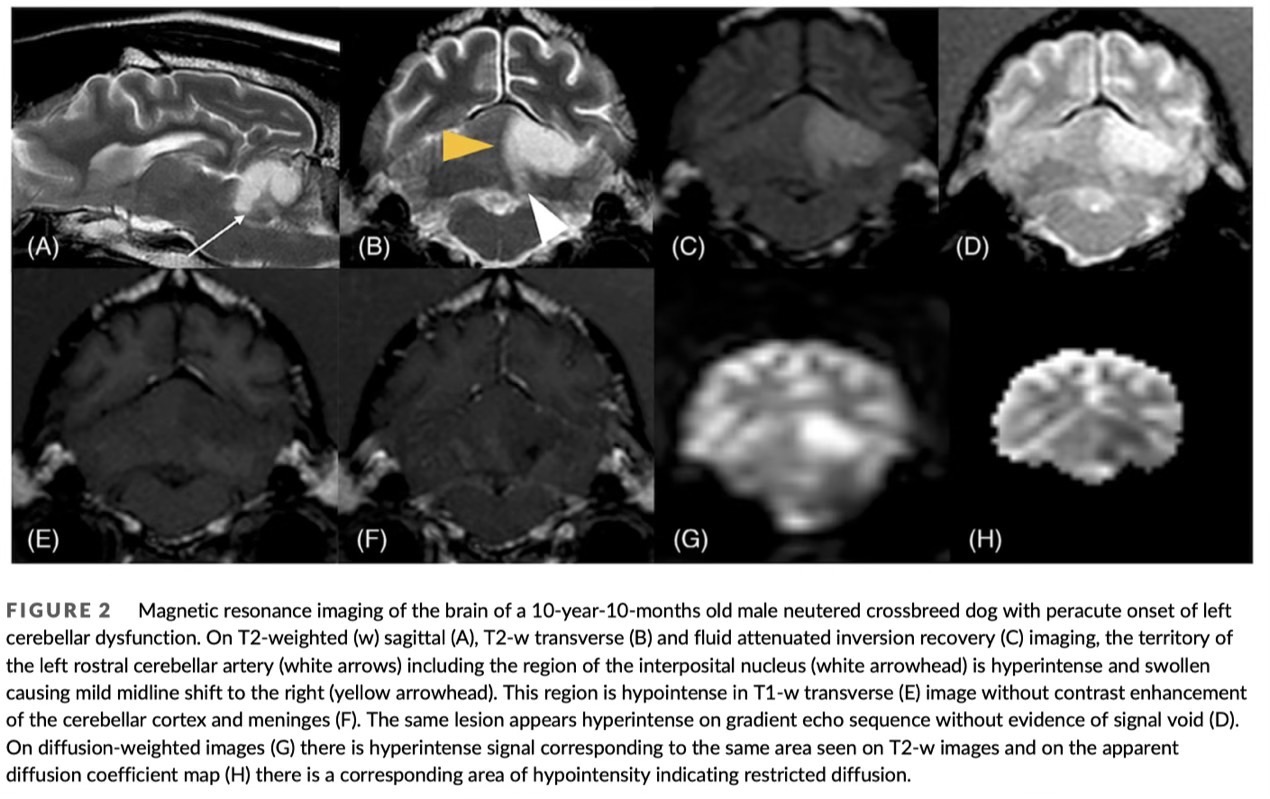

雖然小腦主要負責動作協調,但它可能造成瞳孔大小不一,近年有一篇病歷報告,報導發生在小腦的缺血性中風可能造成同側瞳孔散瞳!

兩隻病例都出現:

- 單側散瞳

- 前庭症狀

- 單側威嚇反應消失

- 腦定位的神經學異常

最後均經由 MRI 確診為小腦梗塞。

若瞳孔異常伴隨「搖晃步態、前庭症狀」,影響小腦的疾病是重要可能原因。

圖三:病歷報告中一隻米可斯犬與一隻靈緹犬均出現左眼散瞳症狀。

圖四:上述米可斯犬的MRI影像,診斷為左側小腦缺血性中風。

文獻:

Mydriasis associated with ischemic cerebrovascular infarct affecting the ipsilateral cerebellar interposital nucleus in 2 dogs(2024)